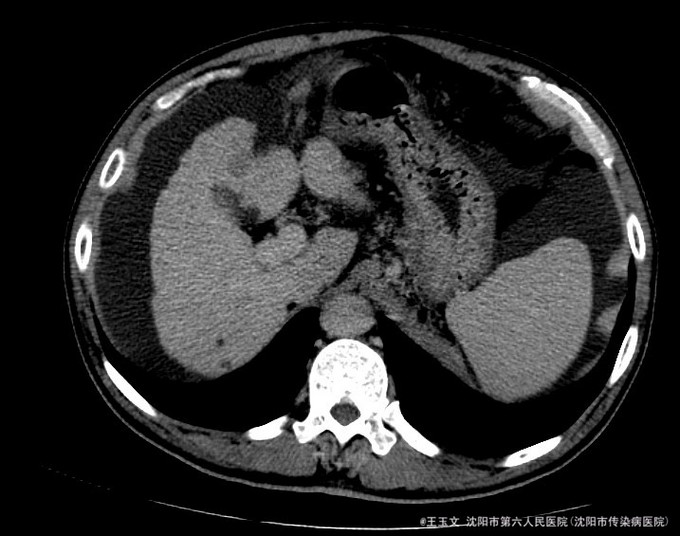

查体:神志清,巩膜无黄染,心肺听诊无异常,腹软,无压痛,肝区无叩痛,移动性浊音阳性,双下肢无浮肿,扑翼样震颤阴性。可见肝掌和腹水等阳性体征 化验结果:天门冬氨酸氨基转移酶 48 U/L、胆碱酯酶 3254 U/L、总蛋白 84.0 g/L、总胆红素 39.9 umol/L、非结合胆红素 26.7 umol/L。凝血酶原时间 15.5 秒、凝血酶原比率 1.35 、凝血酶原百分活动度 54.9 %、活化部分凝血酶原时间 40.7 秒、纤维蛋白原含量 1.255 g/L、D-二聚体 3.05 ug/ml↑。乙型肝炎病毒表面抗原 阳性(+) ↑、乙型肝炎病毒e抗体 阳性(+) ↑、乙型肝炎病毒核心抗体 阳性(+) 。甲胎蛋白(AFP) 11.52 ng/mL。 超声检查示:肝硬化,较多腹水,肝内见多个低回声,较大约1.5*1.0厘米,边界清晰。 肝增强ct:肝脏边缘欠规整,肝裂增宽,各叶大小比例失调,肝实质内见多个低密度结节,较大位于Ⅳ段,大小约2.04cm,增强扫描动脉期Ⅳ段两个结节中等强化,门脉期及延迟扫描呈低密度,余结节无明显强化;肝内亦见多个小囊性密度灶,较大约1.44cm,无强化。肝内外门静脉显示清晰,脾脏增大增厚,超过肝脏下缘,胆囊不大,壁增厚,其内密度均匀,胰腺形态密度无特殊。肝内外胆管未见明显扩张,腹膜后未见明显肿大淋巴结。食管下段胃底贲门区见扩张扭曲的血管影。肝周及腹膜间隙见有中等量液性密度影。

诊断:初步诊断:1、乙肝肝硬化 失代偿期; 确定诊断:乙肝肝硬化 活动性 失代偿期C-P B级 行肝脏增强CT后补充诊断:肝占位性位病变 行DSA下肝动脉造影后修订诊断:原发性肝癌 治疗:限盐饮食,口服利尿剂,减少水钠储留,促进腹水消退,静点异甘草酸镁保肝治疗,行增强CT检查,发现肝内占位,考虑恶性可能大,患者肝功改善后,于局麻下DSA下行肝动脉造影及TACE治疗

术后患者未见TACE治疗并发症,无不适,复查化验结果:天门冬氨酸氨基转移酶 41 U/L、胆碱酯酶 1901 U/L、白蛋白 29.3 g/L、总胆红素 24.6 umol/L。甲胎蛋白测定:甲胎蛋白(AFP) 7.75 ng/mL。患者肝功改善,术后一周时候复查CT示病灶碘油沉积尚好,办理出院。 本例患者比较典型,虽然其术前甲胎蛋白不高,但其增强CT有典型的“快进快出”特征,并且乙肝背景,有经验的医师会考虑其为原发性肝癌的可能非常大, TACE治疗即可以确诊其肝癌,又能在确诊的同时给予治疗。